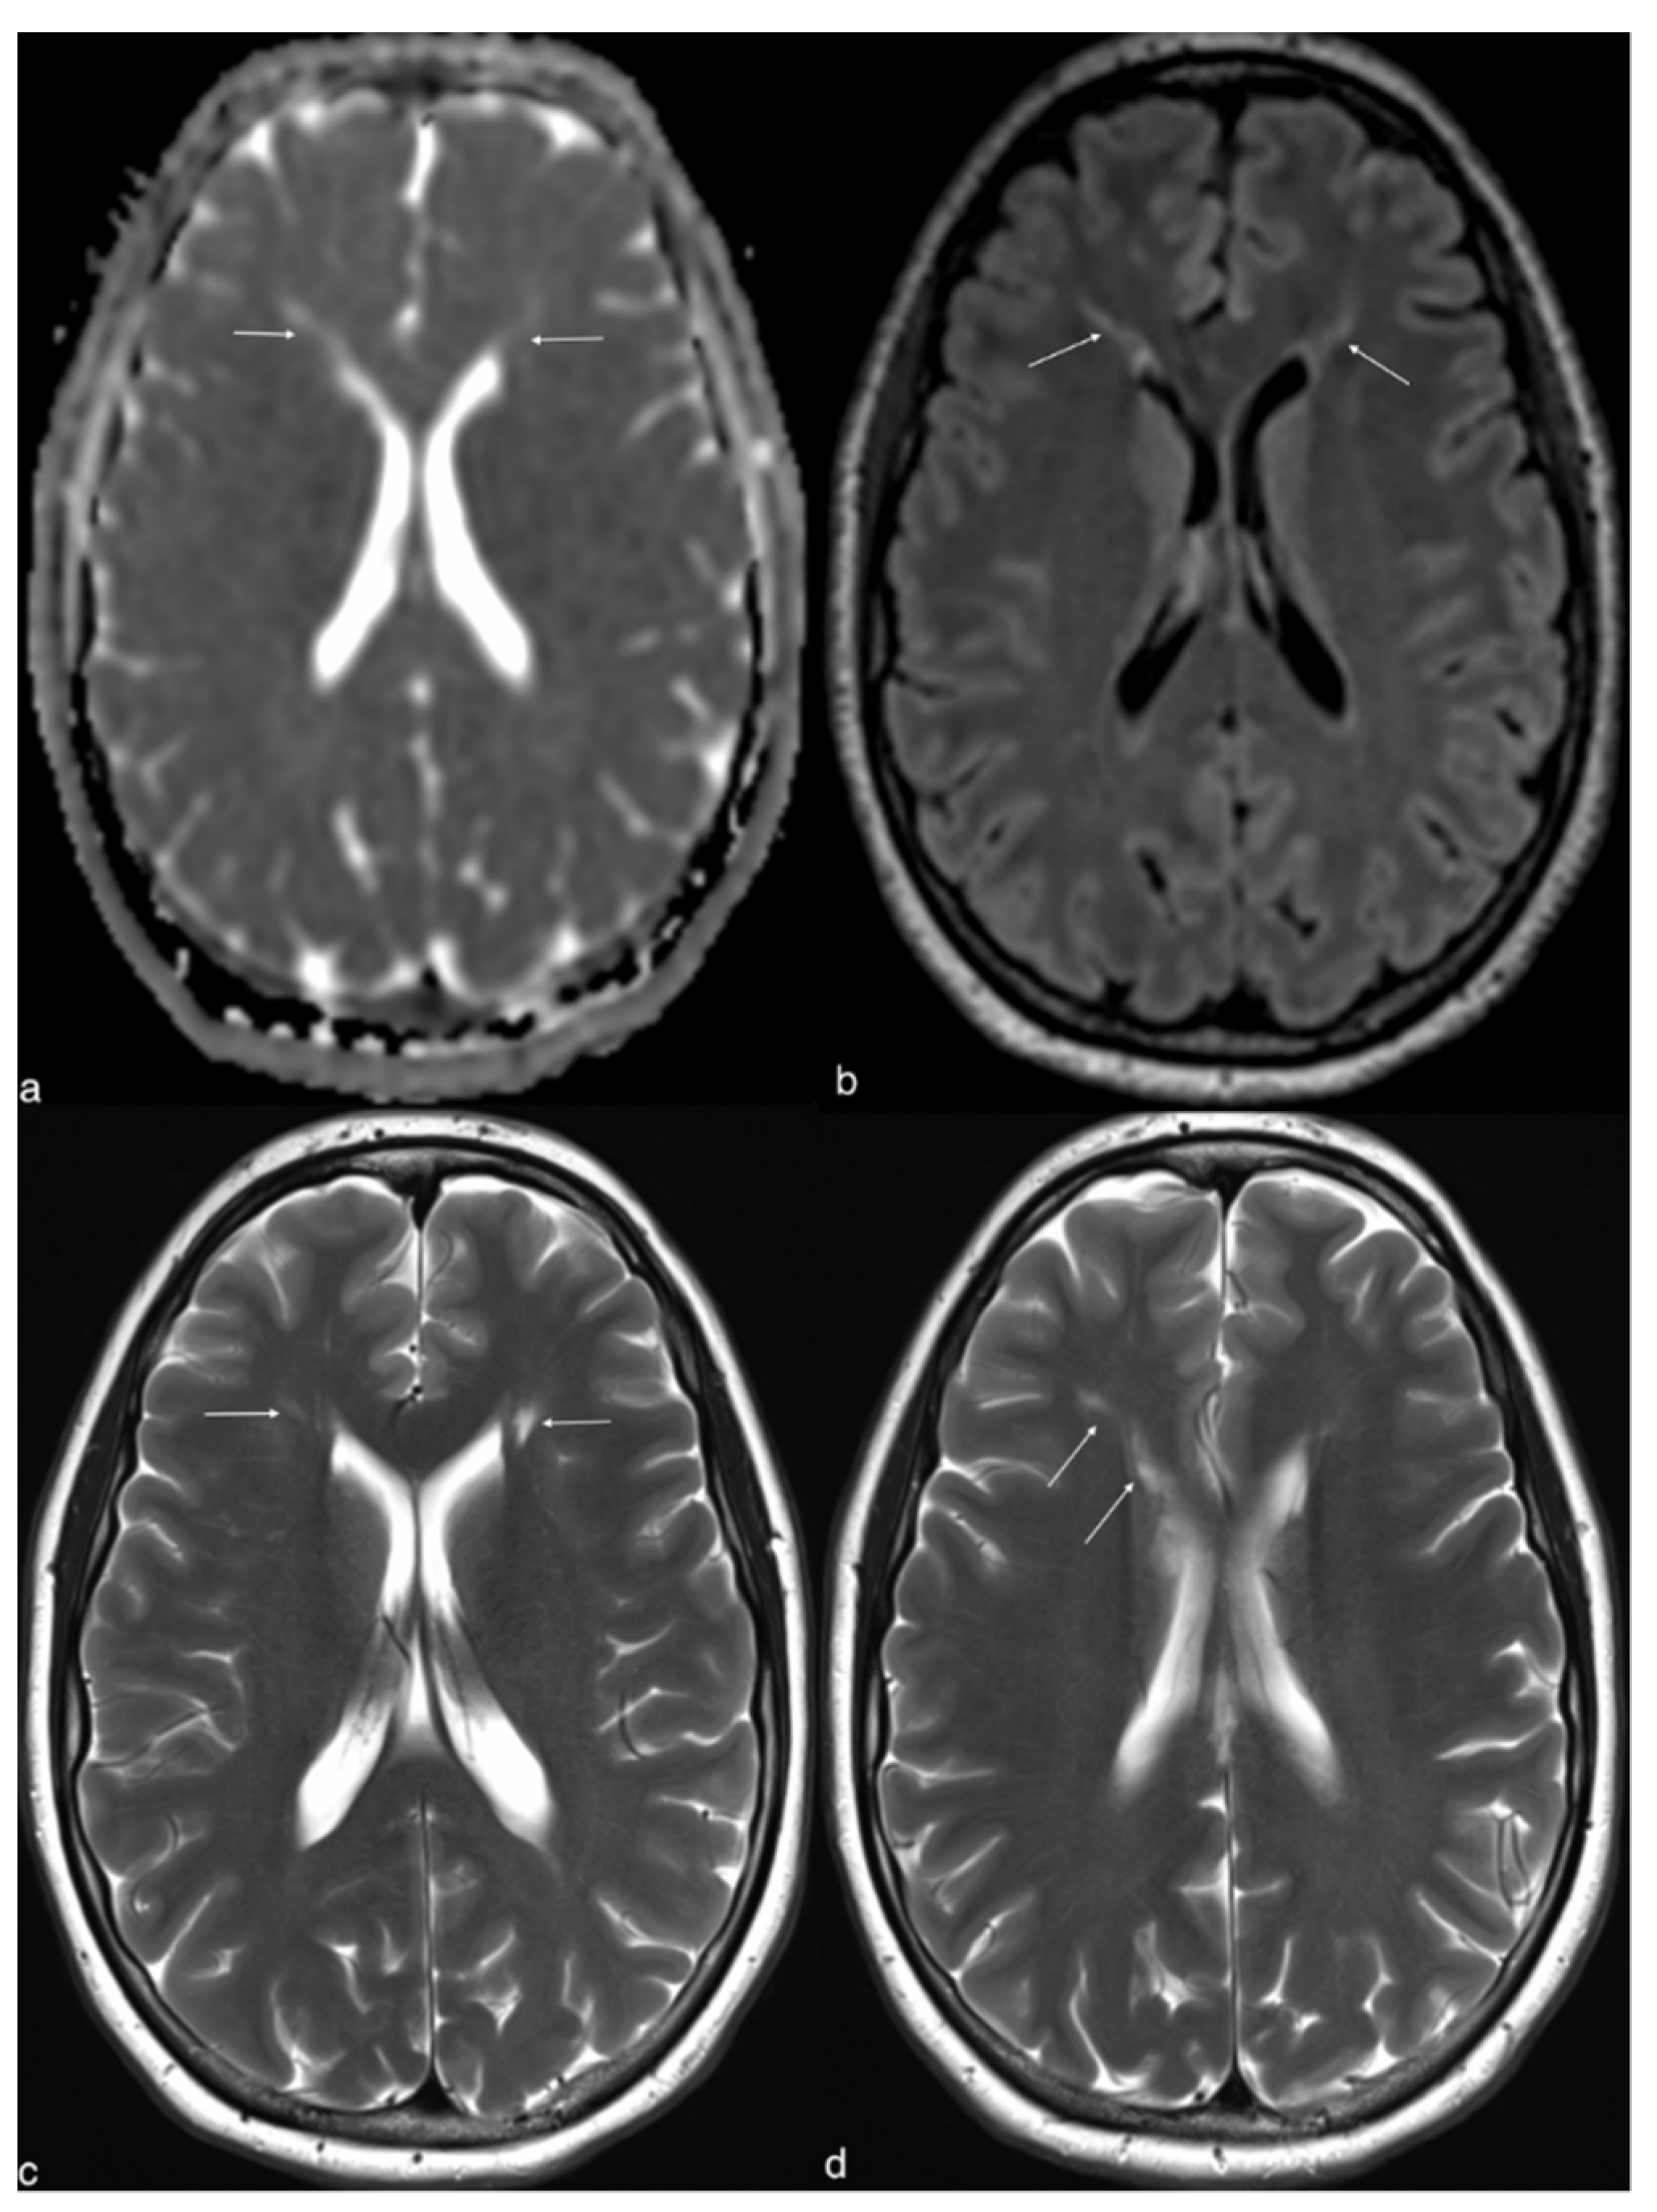

2. Case Report